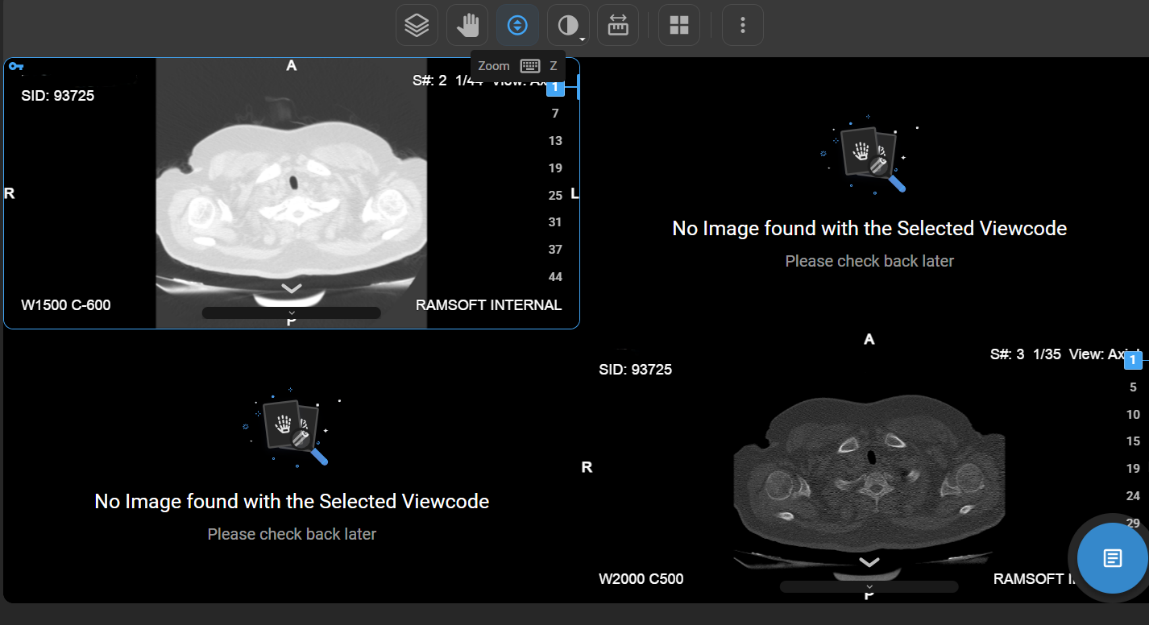

How Do I Zoom In/Out?

• Usage: Change the scale of the image.

• Operation: Right-click and drag.

• Hotkey: Press Z.

• Clinical Utility: Essential for examining fine details (e.g., micro-calcifications, tissue structures).